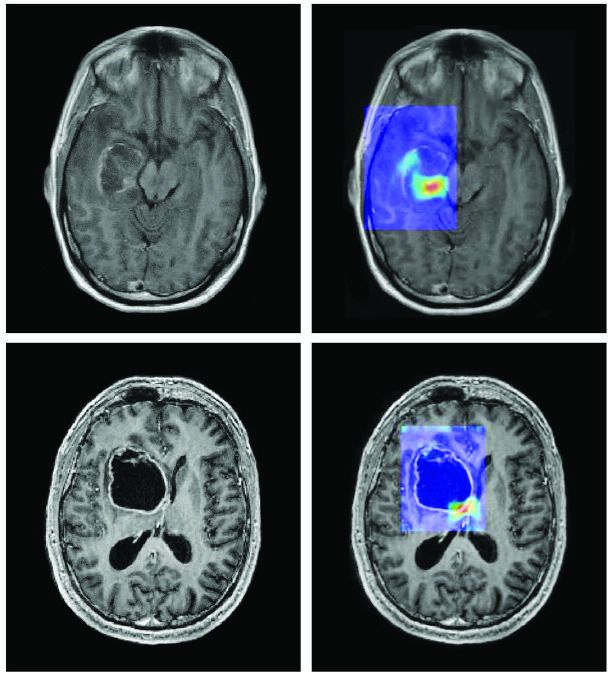

Un algoritmo de aprendizaje profundo programado para analizar imágenes por resonancia magnética pronostica una mutación en el gen IDH1 en los tumores de encéfalo.

Fuente: Fuente: CA Cancer J. Clin., marzo/abril de 2019. doi: 10.3322/caac.21552. CC BY 4.0.